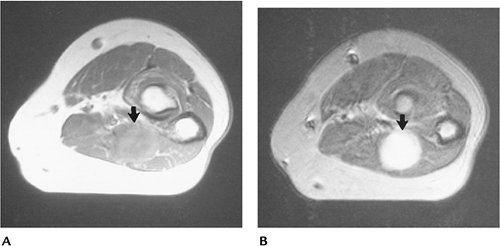

FIGURE 10-47 Lymphangioma. Axial (A) and coronal (B,C) images of the lower extremities demonstrating low signal intensity dilated lymphatic vessels on the right.